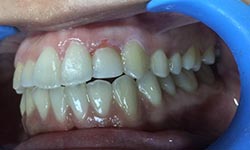

(10) Dental Implant - Full Mouth

Before Treatment

After Treatment

Patient came with a problem in chewing food and multiple loose teeth in upper and lower jaw and was interested in getting a whole new set of teeth in both the jaws. So after removal of all the weakened teeth and placement of multiple implants, he was given implant supported bridge.